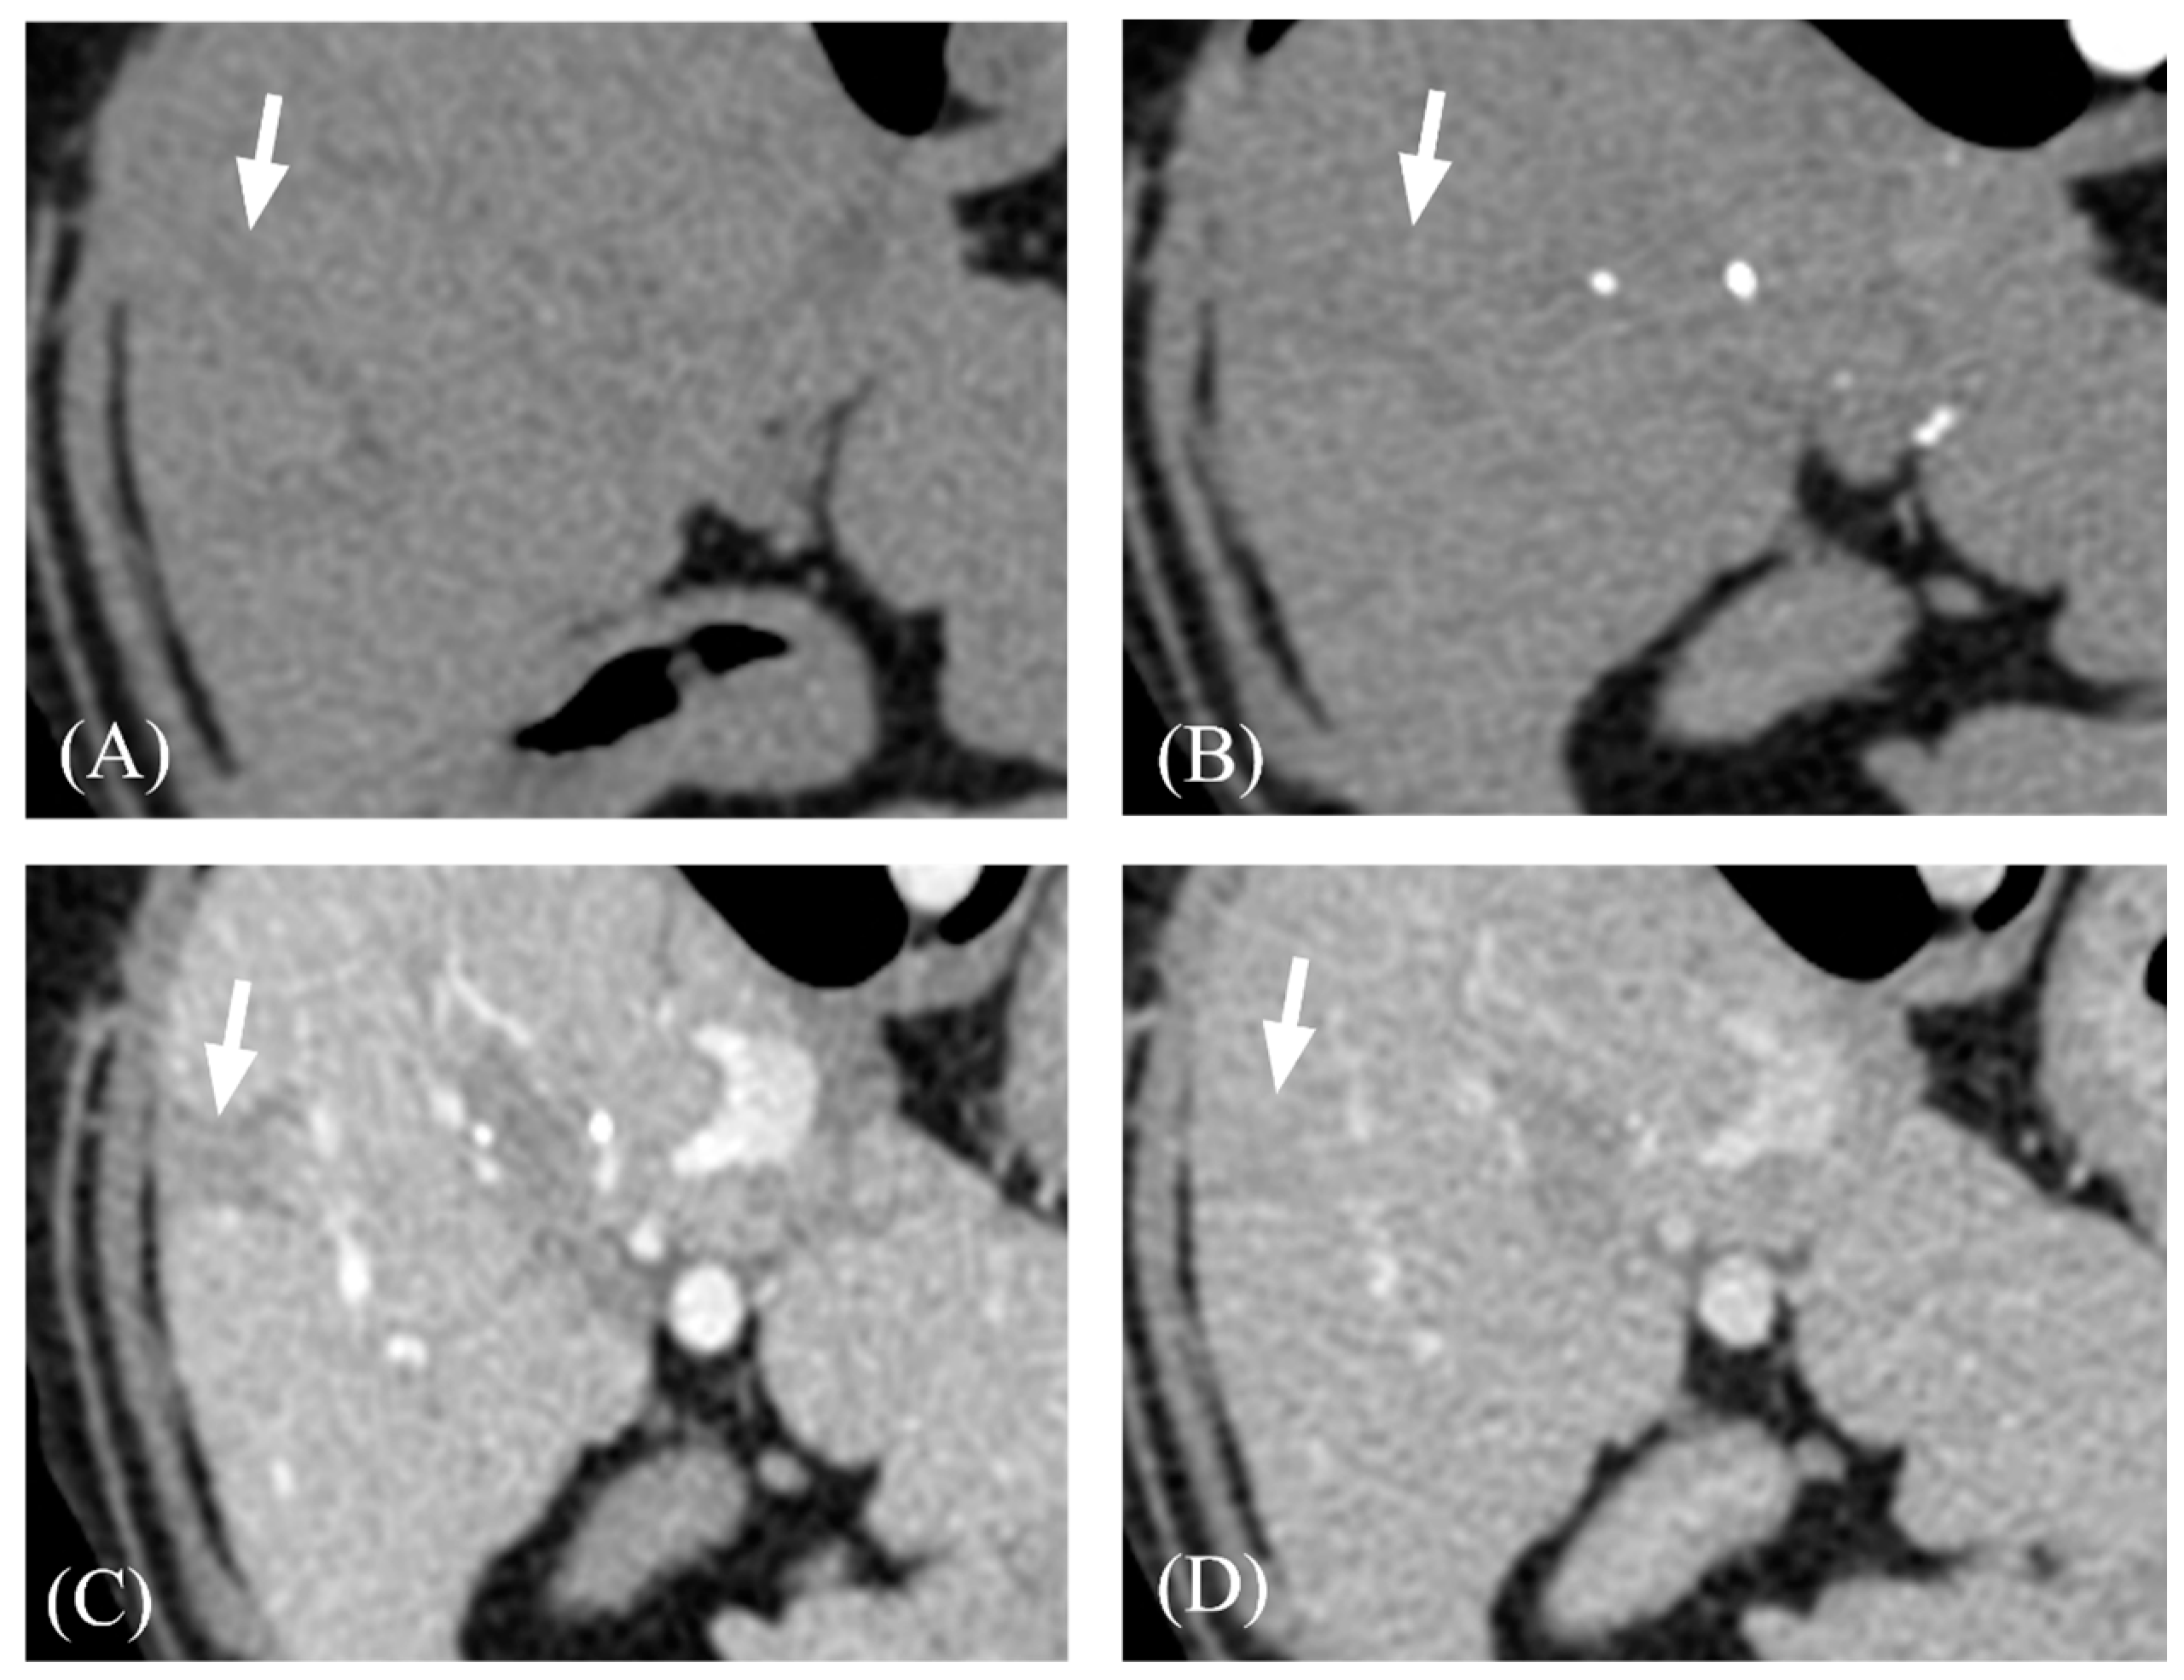

| Transient hepatic attenuation difference | Present | 7/13 (53.8%) | 4/8 (50%) | 3/5 (60%) | 1.000 |

| Absent | 6/13 (46.2%) | 4/8 (50%) | 2/5 (40%) |

- Yamasaki, M.; Furukawa, A.; Murata, K.; Morita, R. Transient Hepatic Attenuation Difference (THAD) in Patients without Neoplasm: Frequency, Shape, Distribution, and Causes. Radiat. Med. 1999, 17, 91–96. [Google Scholar]

- Colagrande, S.; Centi, N.; Carmignani, L.; Salvatori Politi, L.; Villari, N. Meaning and Etiopathogenesis of Sectorial Transient Hepatic Attenuation Differences (THAD). Radiol. Med. 2003, 105, 180–187. [Google Scholar]